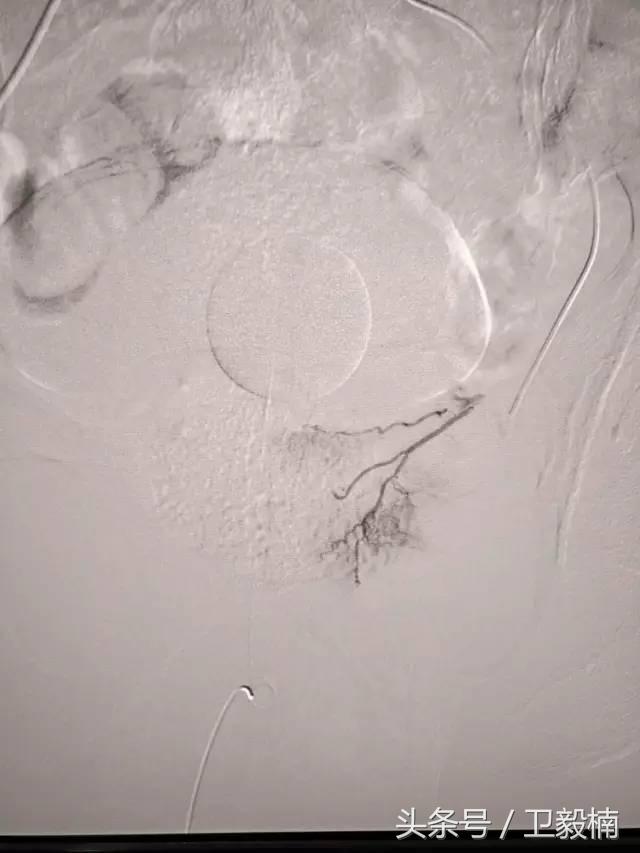

二、各类肿瘤的治疗:如肝癌、肺癌、食管癌、肾癌、胰腺癌、各种转移性肿瘤及妇科肿瘤、骨肿瘤等;

三、肝血管瘤栓塞术、肾错构瘤栓塞术和肝、肾囊肿、脓肿抽吸硬化术等;

(1)选择性肿瘤供血动脉灌注化疗+栓塞治疗恶性肿瘤。

(3)应用栓塞术治疗海绵状血管瘤,蔓状血管瘤,子宫肌瘤,骨肉瘤,鼻咽部纤维血管瘤等。